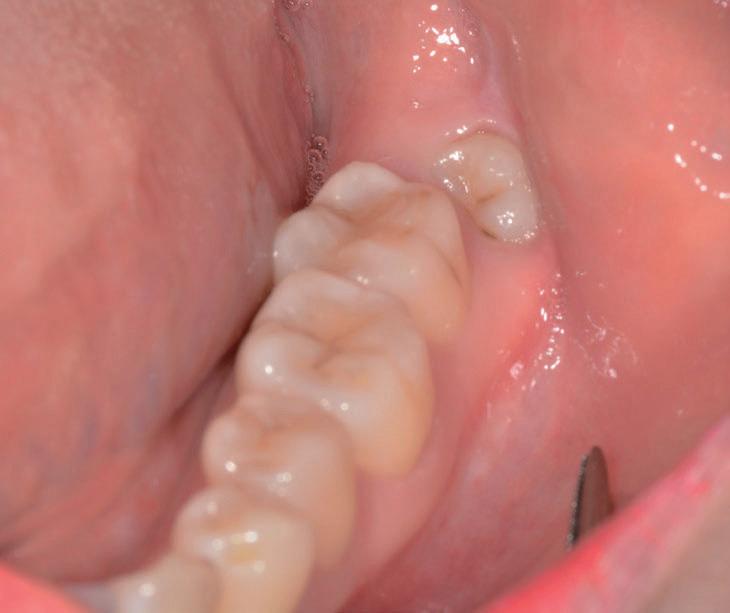

Questo è un paziente di 22 anni ed essendo un amico, ho potuto ben documentare il caso con il suo consenso: il suo dente del giudizio inferiore sinistro è stato estratto utilizzando il manipolo dritto. Figg. 143-149

Figg. 143-149 - Caso 1, paziente di 22 anni: tecnica di estrazione con divisione orizzontale utilizzando il manipolo dritto. Fig. 143 Fig. 144 Fig. 145 Fig. 146 Fig. 147 Fig. 148 Fig. 149